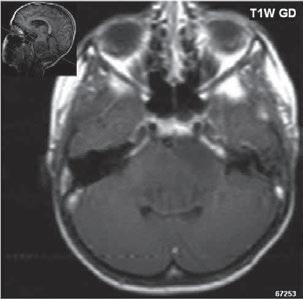

I.11 Patologické procesy selární oblasti . . . . 309

I 11 3 Makroadenom hypofýzy

Optochiasmaticko-hypothalamický gliom